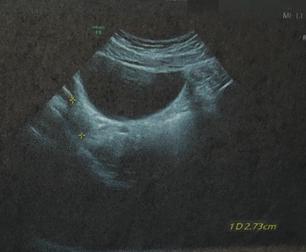

小温既往无病史,并且也无妇科肿瘤相关的家族史,月经一直都很规律,并且除了小腹坠痛,无其他症状。入院时,小温的腋温37.3℃,稍高。于是我让小温去做了相关的实验室检查和影像学检查,白细胞11*10⁹/L,人绒毛膜促性腺激素(HCG)阴性,超声可见左侧附件低回声区,边缘清晰,提示:左侧卵巢囊肿(畸胎瘤的可能性大)。